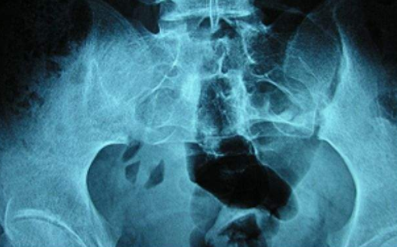

郑州强直性脊柱炎诊疗中心医院介绍到强直性脊柱炎影像学表现主要分为两个部位。骶髂关节的影像学改变。骶髂关节的影像学改变是强直性脊柱炎最早出现的变化,一般可以通过x线片检查发现骶髂关节骨缘模糊,骨...[详细]